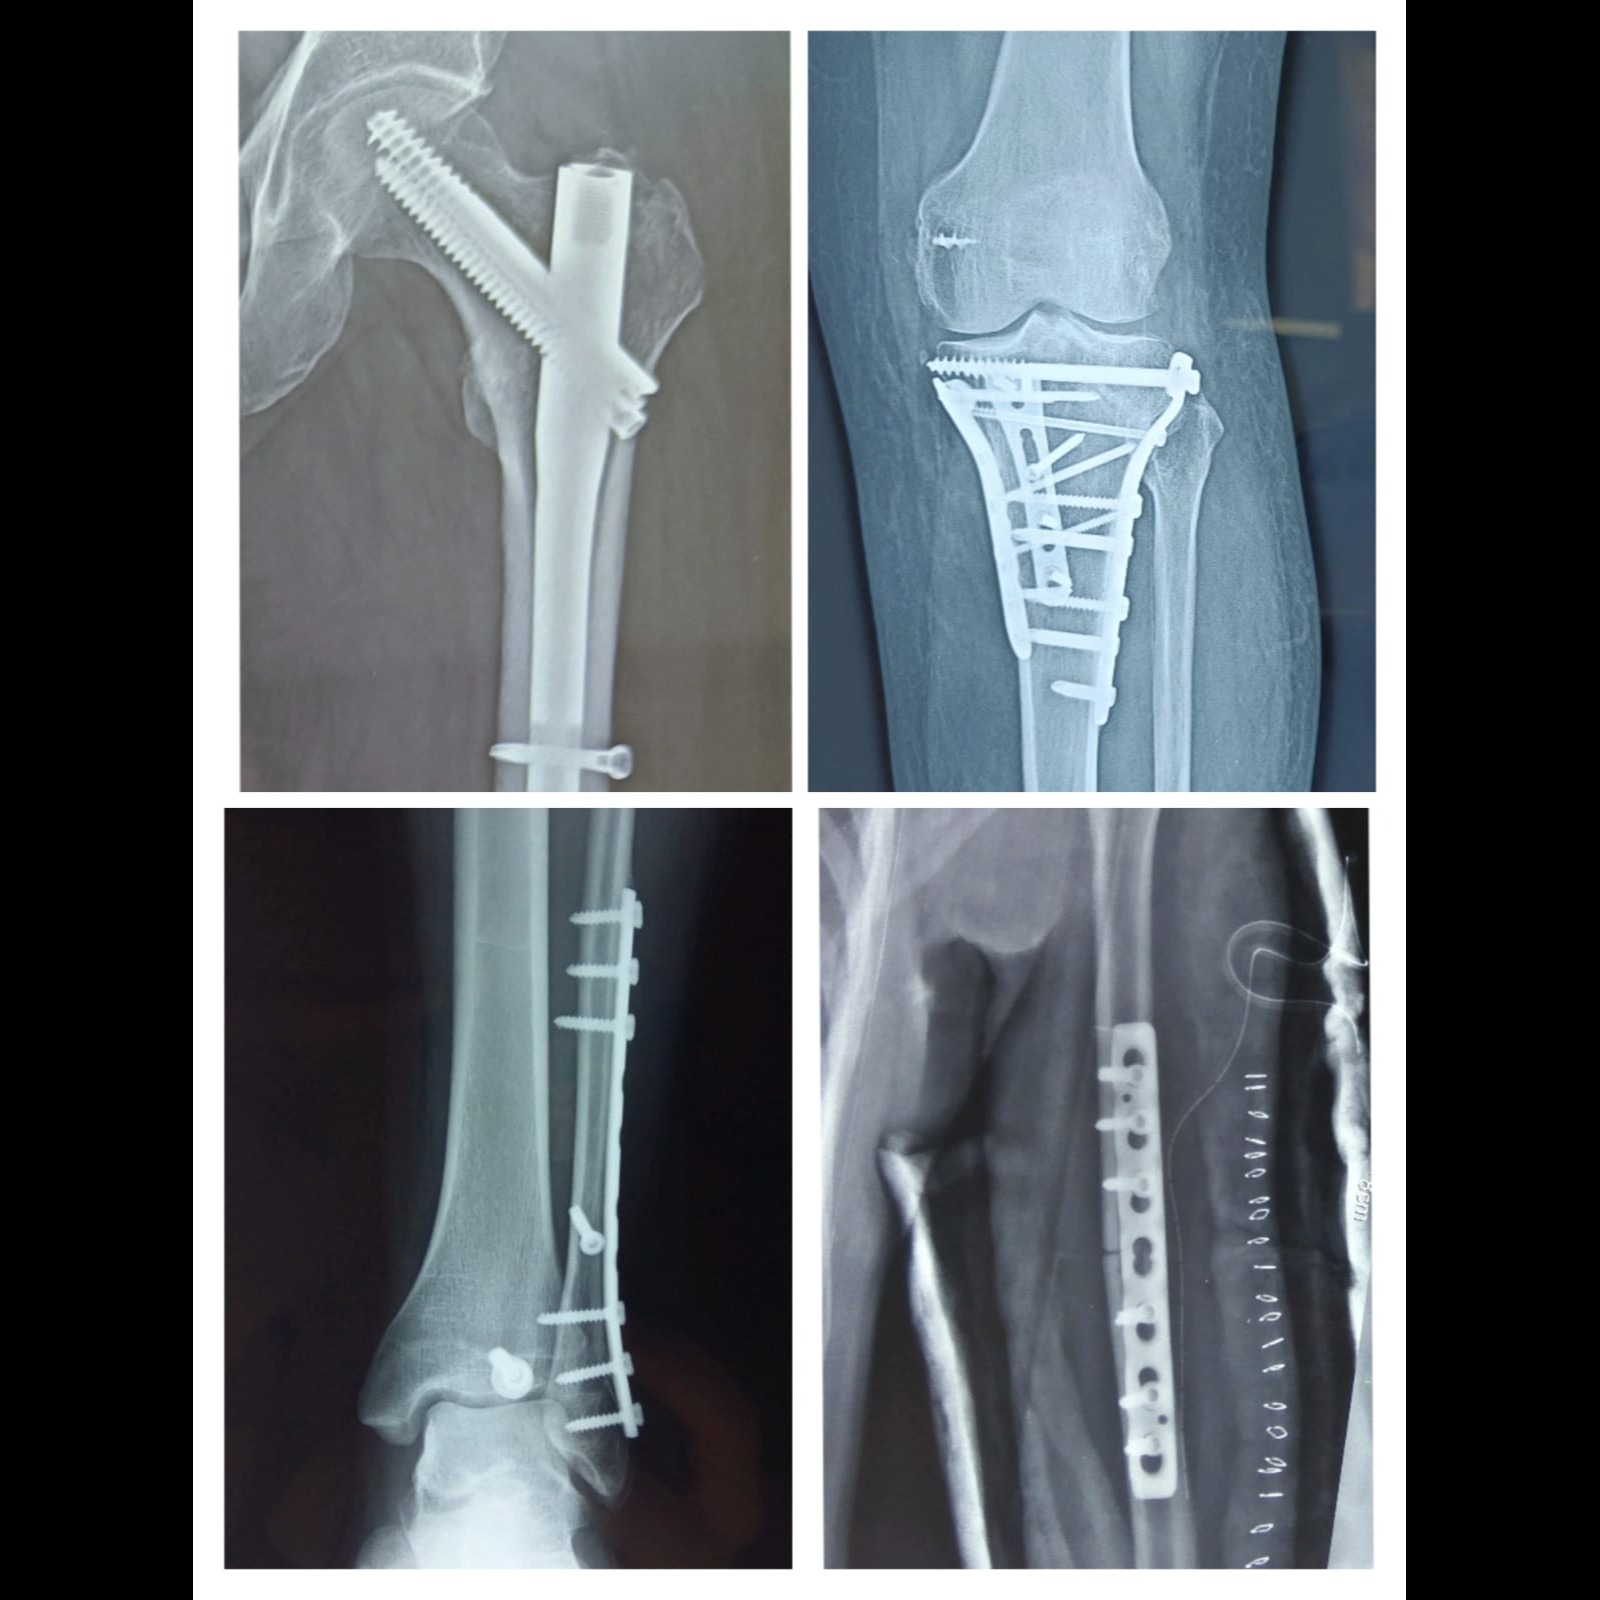

Dr. Atul Sonawane - Othopedic, Fracture, Sports injury, Joint replacement and Arthroscopy specialist